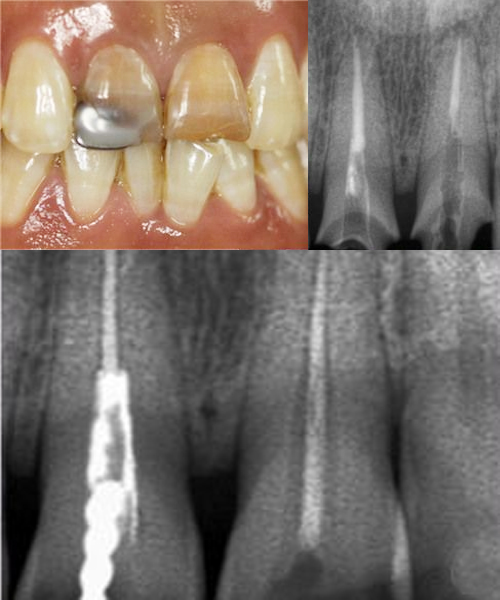

一患者上颌切牙外伤,在外院修复后因变色影响美观,来我院要求重新修复。X线检查发现根充不完善。经植入纤维桩、排龈后恢复牙冠外形、精修肩台、抛光牙体等后,更换新烤瓷牙。经过治疗后的牙齿,分辨不出真、假,患者非常满意。

X线检查